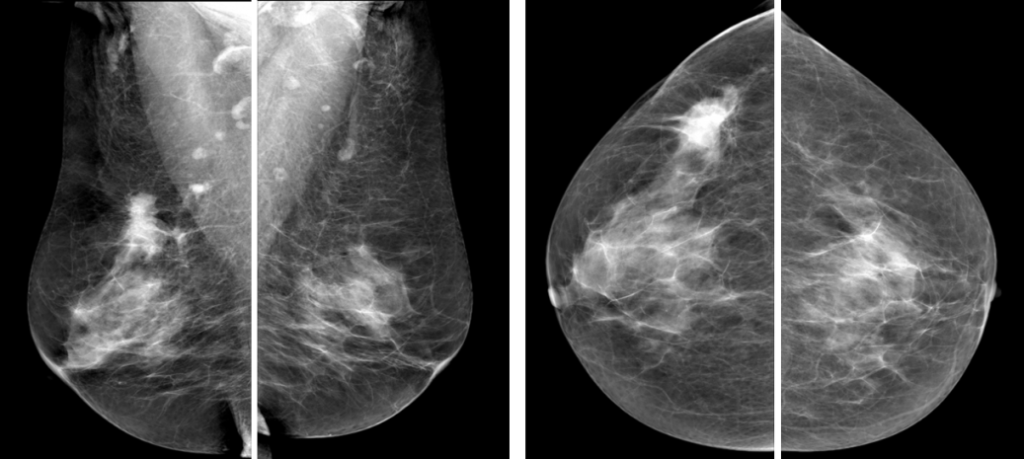

Рис.1 Маммография, выполненная в двух проекциях: фиброаденома левой молочной железы

Рис.2 Маммография, выполненная в двух проекциях: рак правой молочной железы